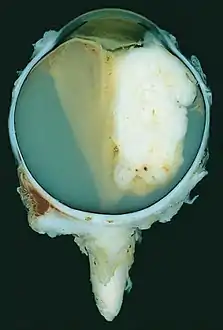

A pathology specimen of a retinoblastoma tumor from an enucleated eye of a 3-year-old female

Morphology

Gross and microscopic appearances of retinoblastoma are identical in both hereditary and sporadic types. Macroscopically, viable tumor cells are found near blood vessels, while zones of necrosis are found in relatively avascular areas. Microscopically, both undifferentiated and differentiated elements may be present. Undifferentiated elements appear as collections of small, round cells with hyperchromatic nuclei; differentiated elements include Flexner-Wintersteiner rosettes, Homer Wright rosettes,[29] and fleurettes from photoreceptor differentiation.[30]